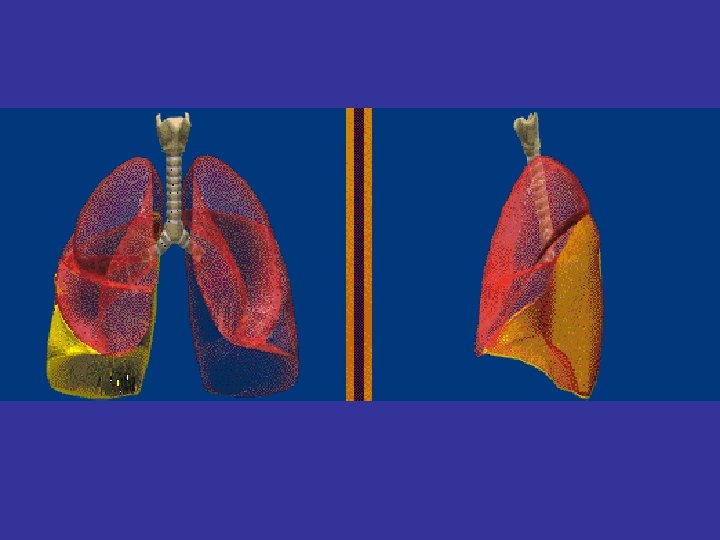

Lobes and Fissures

lateral view ? ! can detect otherwise hidden masses

The lateral chest film our best friend • Find abnormalities on the frontal film

The lateral chest film our best friend • Find abnormalities on the frontal film • Confirm abnormalities suspected from frontal film • Don’t be afraid to look at it